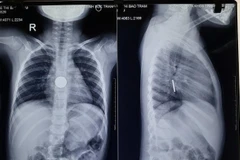

Phẫu thuật nội soi cắt thành công khối u vỏ bao thần kinh hiếm gặp

Đây là ca mổ khó do khối u nằm gần nhiều cấu trúc quan trọng như động mạch và tĩnh mạch dưới đòn, thần kinh hoành, thần kinh X, ống ngực và chuỗi hạch giao cảm cổ-ngực.